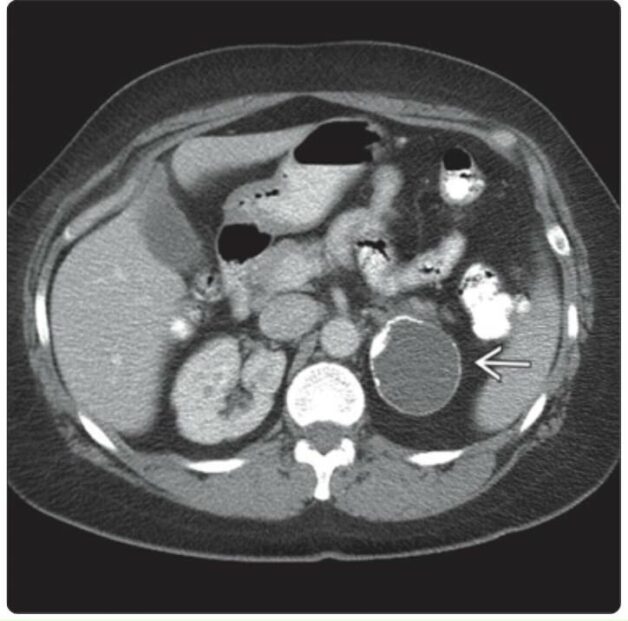

Trong tổng số các tổn thương, u bạch huyết hoặc u nang nội mô chiếm gần 45%, thường có kích thước nhỏ, đường kính thường dao động từ 0,1 đến 1,5 cm. Điều này thường làm cho các căn bệnh này trở nên khó nhận biết bằng các phương pháp thông thường. Đôi khi bệnh chỉ có thể được phát hiện thông qua các phương pháp hình ảnh y tế chính xác như siêu âm, CT scan, hoặc MRI.

Ngoài ra, một loại tổn thương khác là các nang giả của tuyến thượng thận chiếm phần lớn tổn thương, khoảng 39%. Đây thường là những cấu trúc không có lớp biểu mô, chúng có thể là kết quả của các đợt xuất huyết trước đó trong tuyến thượng thận. Việc phân loại và hiểu rõ về các loại tổn thương này đóng vai trò quan trọng trong quá trình chẩn đoán, điều trị bệnh lý.